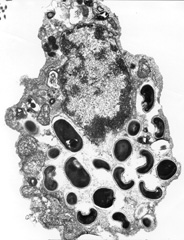

Many microsporidian genera multiply and mature while floating free among the intracellular organelles within the host cell's cytoplasm. Other genera develop within either a host-produced vacuole (Encephalitozoon) (Fig. 2) or a parasite-produced envelope (Pleistophora).

Fig. 2. Electron micrograph of a eukaryotic host cell that contains Encephalitozoon intestinalis spores and developing forms inside a septated parasitophorous vacuole. Reprinted from the Parasite Image Library of the Centers for Disease Control and Prevention Website on Laboratory Identification of Parasites of Public Health Concern (DPDx). (Available at http://www.dpd.cdc.gov/dpdx/HTML/ImageLibrary/Microsporidiosis_il.htm accessed February 17, 2005.)